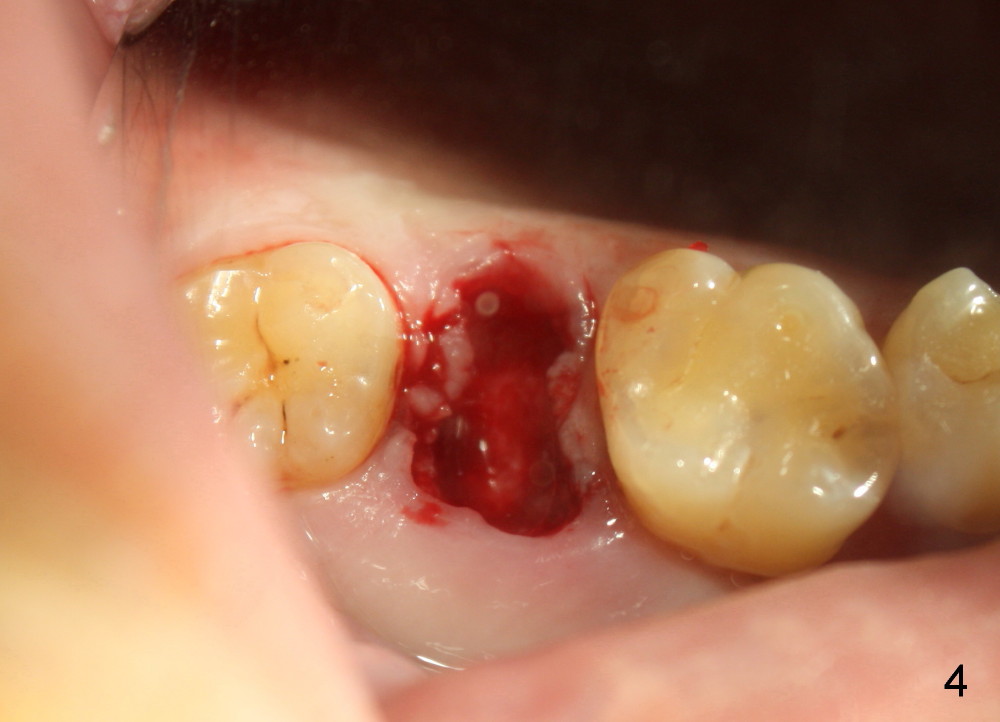

A 42-year-old man is afraid of dentistry. Residual roots of #2 remain untreated for at least 2.5 years (Fig.1). Both the mesiodistal space and the height are limited and unfavorable to restoration (Fig.2,3). Finally he agrees to have treatment, since the tooth #15 is worn so much that it is sensitive to mastication. When the tooth #2 is extracted, the socket is triangular without septum (Fig.4); the bottom of the socket is flat and easy for osteotomy. A 5x17 mm tap has obtained stability once it is placed ~ 14 mm deep (Fig.5). A 5x14 mm implant is placed with insertion torque > 60 Ncm (Fig.6 I), followed by placement of 4x3 mm abutment (A).